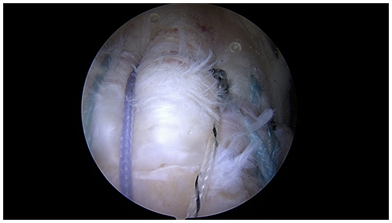

All transosseous techniques offer several permutations and combinations of suture patterns. The simple repair, the box repair, and the X box repair, are demonstrated in Figure 2. These techniques allow for multiple small diameter fixation points to create whichever fixation pattern the surgeon chooses as appropriate.

Figure 2 Various all transosseous repairs: a) simple b) X box c) three tunnel.